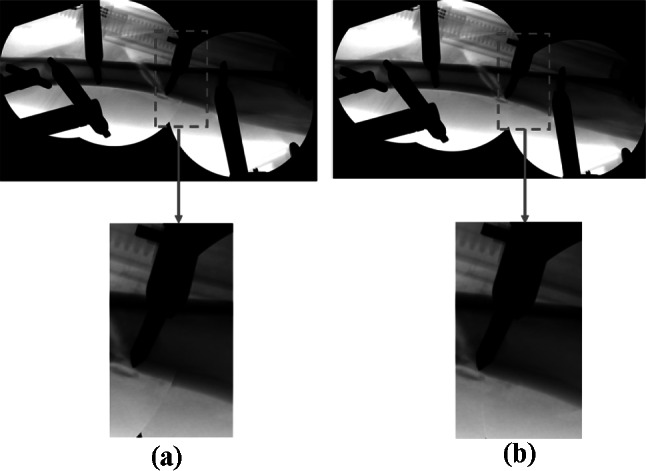

Figure 6 shows the comparison of a stitched region in the X-ray images of the caprine tibia acquired using both the hybrid method and the proposed method. As shown in Fig. 4, these were the only two methods that can construct a successful panoramic X-ray image of a caprine tibia with fixation pins. However, there was a little difference in the quality of the panoramic X-ray images. When the stitched region indicated by a red dotted line was magnified, the result from the proposed method was more natural than the hybrid method and did not have a boundary effect. Since more matched features can be acquired from the integrated feature matching, a more precise homography was estimated using the proposed method.

Fig. 6.

Comparison of a stitched region in X-ray images of a caprine tibia (with fixation pins): (a) hybrid and (b) proposed methods